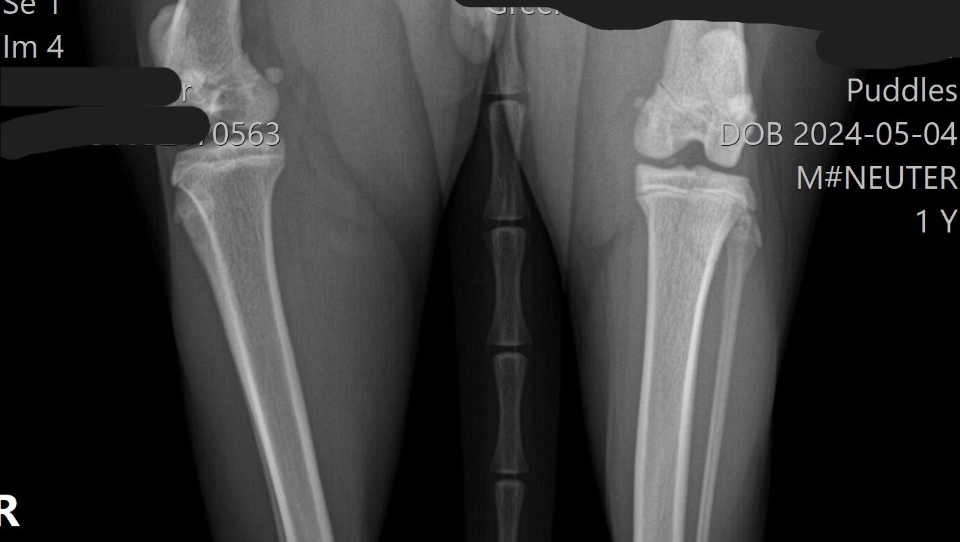

Xrays ⬇️

We rushed him to the vet the next day. That alone cost nearly $700, which completely drained us. They did X-rays and gave him pain meds, and the next day we got the news: Puddles has a fractured femur near the hip, and he needs a surgery called an FHO (femoral head ostectomy) to be able to walk normally again without pain.